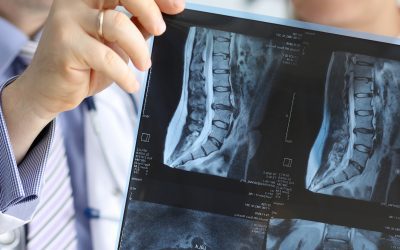

Important Facts About High-field MRI

The strength of an MRI magnet is called “field strength” and is measured in Tesla. The term “High-field MRI” is used when the scanner’s field...

Important Facts About CT Scans

A Computed Tomography which is also more commonly known as a CT or CAT scan, is a Diagnostics test used to create detailed images of internal...